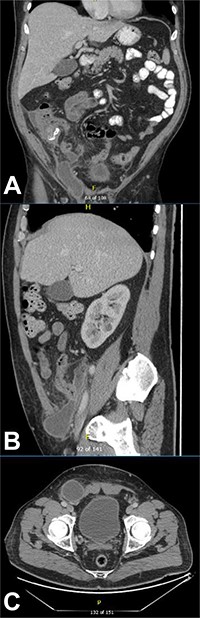

CT of the abdomen and pelvis demonstrating a fluid collection/abscess extending into a right inguinal hernia sac in (A) coronal (B) sagittal and (C) apical planes.

He had ongoing episodes of fever (38.1, 38.8 and 38.5°C) on days 3 and 4 post-operatively, so his antibiotics were escalated to piperacillin/tazobactam and metronidazole, according to microbiologist advice. However, on day 5 post-operation, he was still complaining of a severe tenderness on the right iliac fossa, associated with guarding, he was diaphoretic and febrile and clinical examination showed a tender lump in the right inguinal region. A CT of the abdomen and pelvis was performed to assess for a deep-seated collection, and it showed post-operative changes in the right lower quadrant at the site of recent appendicectomy, with small foci of poorly encapsulated fluid in the right lower quadrant with a further more well-defined 7 cm fluid collection/abscess extending from the right lower quadrant into a right inguinal hernial orifice and extending into the hernia sac (Fig. 2).